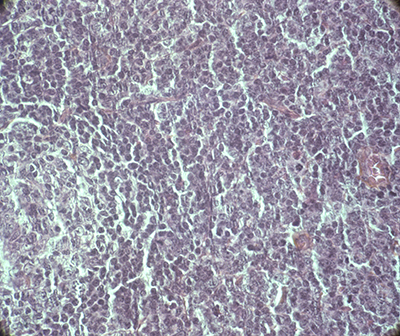

T-PLLs generally have a classic prolymphocytic morphology consisting of medium-sized cells and a high nuclear/cytoplasmic ratio, condensed chromatin, basophilic cytoplasm with cytoplasmic blebs, and a single prominent nucleolus (Figures 1, 2). In half of cases, the cells contain regular, round or oval, nuclei, whereas in the rest, the nuclei are irregular and often convoluted, resembling those seen in Sezary syndrome (Figures 3A, 3B) or ATLL cells (Figure 4). In 25% of cases, the cells are small, indistinguishable from CLL cells, or cerebriform (Figures 2, 5) and the nucleolus is not easily visible by light microscopy, as it is masked by the highly-condensed chromatin [1, 5–7]. Skin lesions are characterized by leukemia cutis with perivascular and periadnexal infiltrates containing irregular, small to medium-sized lymphocytes, without epidermotropism (Figures 6–7). Infiltration of lymph nodes is often diffuse, with paracortical expansion in some cases (Figures 8–9).

Figure 8: Diffuse lymph node infiltrate with paracortical expansion. Persistence of two residual lymphoid follicles (HES,X 5).

Figure 9: Lymph node infiltrate by medium-sized cells with irregular nuclei (HES, X 40).